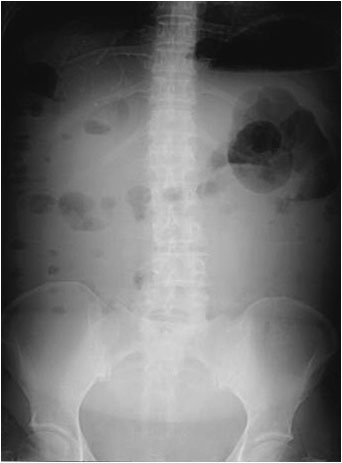

Signo de ascitis en la radiografía simple de abdomen, justificado por la presencia de abundante líquido sobre el que flotan las asas intestinales. En la imagen se observa un aumento de densidad difuso (en “vidrio deslustrado”), y asas agrupadas en posición centroabdominal.

SIGNO DEL ABDOMEN EN VIDRIO DESLUSTRADO

Signo de ascitis masiva en la radiografía simple de abdomen. El signo consiste en el aumento de la densidad abdominal, la borrosidad de los contornos de los órganos intraabdominales y el borramiento de planos grasos, producidos como consecuencia de la presencia del líquido ascítico. El efecto recuerda a una imagen vista a través de un vidrio esmerilado.